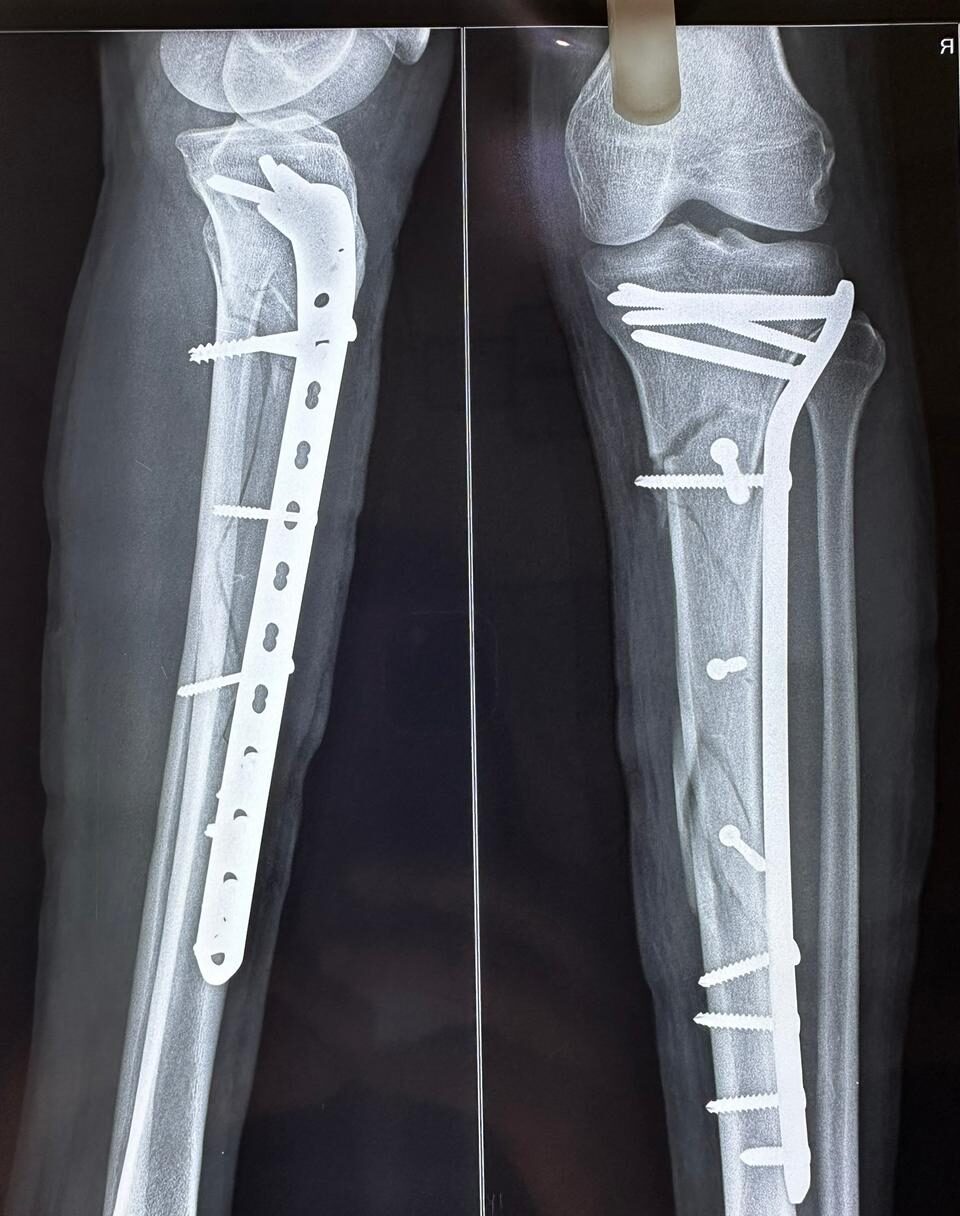

Moments That Mark Meaningful Recovery

Witness real patient transformations at The Ortho Clinic through images that reflect successful treatments and restored mobility.